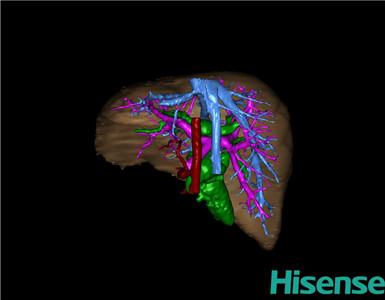

将0.625mm双源薄层CT资料的静脉期和动脉期Dicom格式文件导入海信CAS系统。

通过调节窗宽窗位调整CT序号,对肝实质,胆囊,胆总管,下腔静脉,肝动脉、门静脉及肝静脉等进行三维重建;系统自动计算肝脏体积。

术前三维重建:

重建图片